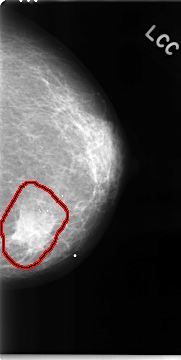

C_0050_1.LEFT_CC

FILE: C_0050_1.LEFT_CC.OVERLAY

TOTAL_ABNORMALITIES 1

ABNORMALITY 1

LESION_TYPE MASS SHAPE IRREGULAR MARGINS SPICULATED

ASSESSMENT 5

SUBTLETY 5

PATHOLOGY MALIGNANT

TOTAL_OUTLINES 1

BOUNDARY

LEFT_CC LINES 4680 PIXELS_PER_LINE 2352 BITS_PER_PIXEL 12 RESOLUTION 50 OVERLAY